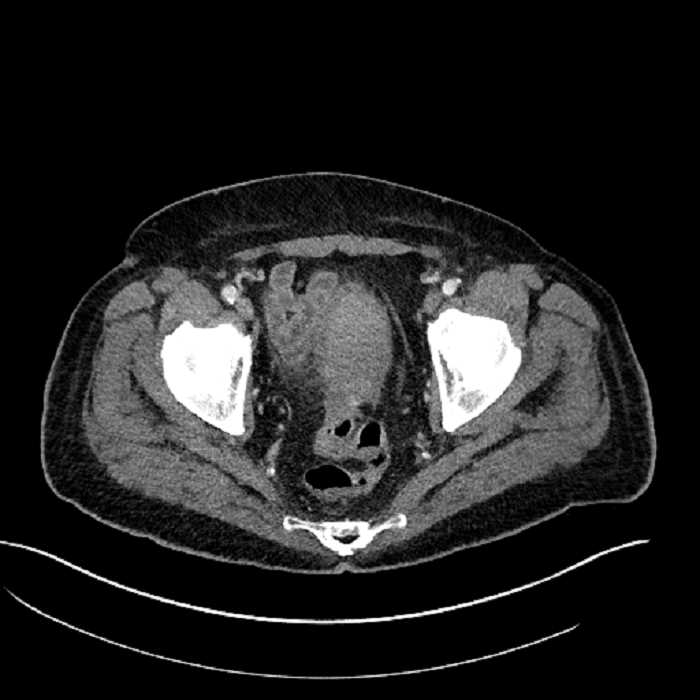

• Large fluid density structure in hepatic segments 7 and 8 measuring 10 x 7 x 7 cm with internal septation and circumferential ill-defined low density compatible with edema

• Peripherally enhancing subcapsular collections along the anterior margin of the left hepatic lobe measuring 3 x 1 cm and 2 x 1 cm

• Clearly marginated fluid density structure in segment 7 and several other scattered tiny hypodensities, which likely represent cysts

• Mild mural thickening of a segment of the sigmoid colon with adjacent fat stranding and a 1.5 cm fluid and gas collection along the tip of an inflamed diverticulum

• Loss of the normal fat plane between this collection and adjacent loops of small bowel, which demonstrate mural thickening

• High grade stenosis of the left common iliac artery, with the left internal and external iliac arteries remaining patent

Acute sigmoid diverticulitis complicated by a small contained perforation and a large abscess in the right hepatic lobe. Additional small subcapsular abscesses along the anterior margin of the left hepatic lobe.

Additionally, loss of the normal fat plane between the peridiverticular collection and adjacent thickened loops of small bowel raises the potential for an enterocolonic fistula.

High grade stenosis of the left common iliac artery. The left external and internal iliac arteries are patent.

• The classic CT imaging appearance is a double target sign with internal low density surrounded by an internal enhancing rim (capsule) and a low density external rim (edema)

Hepatic abscess showing the double target sign with low density internally surrounded by a thin inner enhancing rim (red arrow) and ill-defined outer low density rim (yellow arrow). Blue arrow indicates an internal septation. Red arrows: additional smaller subcapsular abscesses. Red arrow: focal contained perforation associated with diverticulitis.